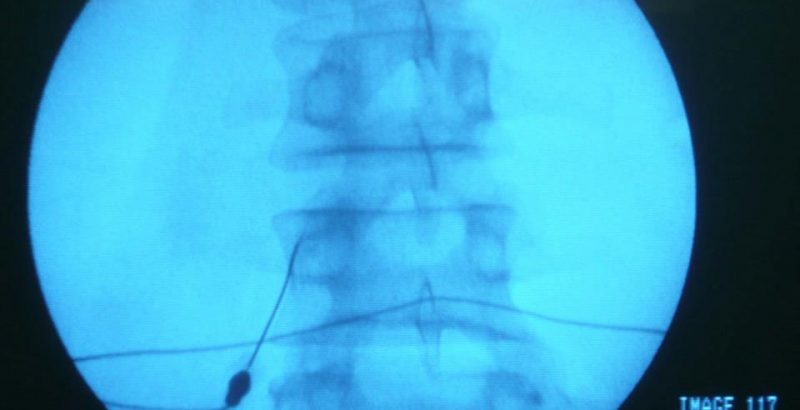

O que é a neuroestimulação? A neuroestimulação é uma técnica médica que utiliza impulsos elétricos de baixa intensidade para modular a atividade do sistema nervoso central e periférico. Ao interferir com os sinais de dor que vão da periferia do nosso corpo para o cérebro, este tratamento oferece um alívio significativo e duradouro para muitas […]